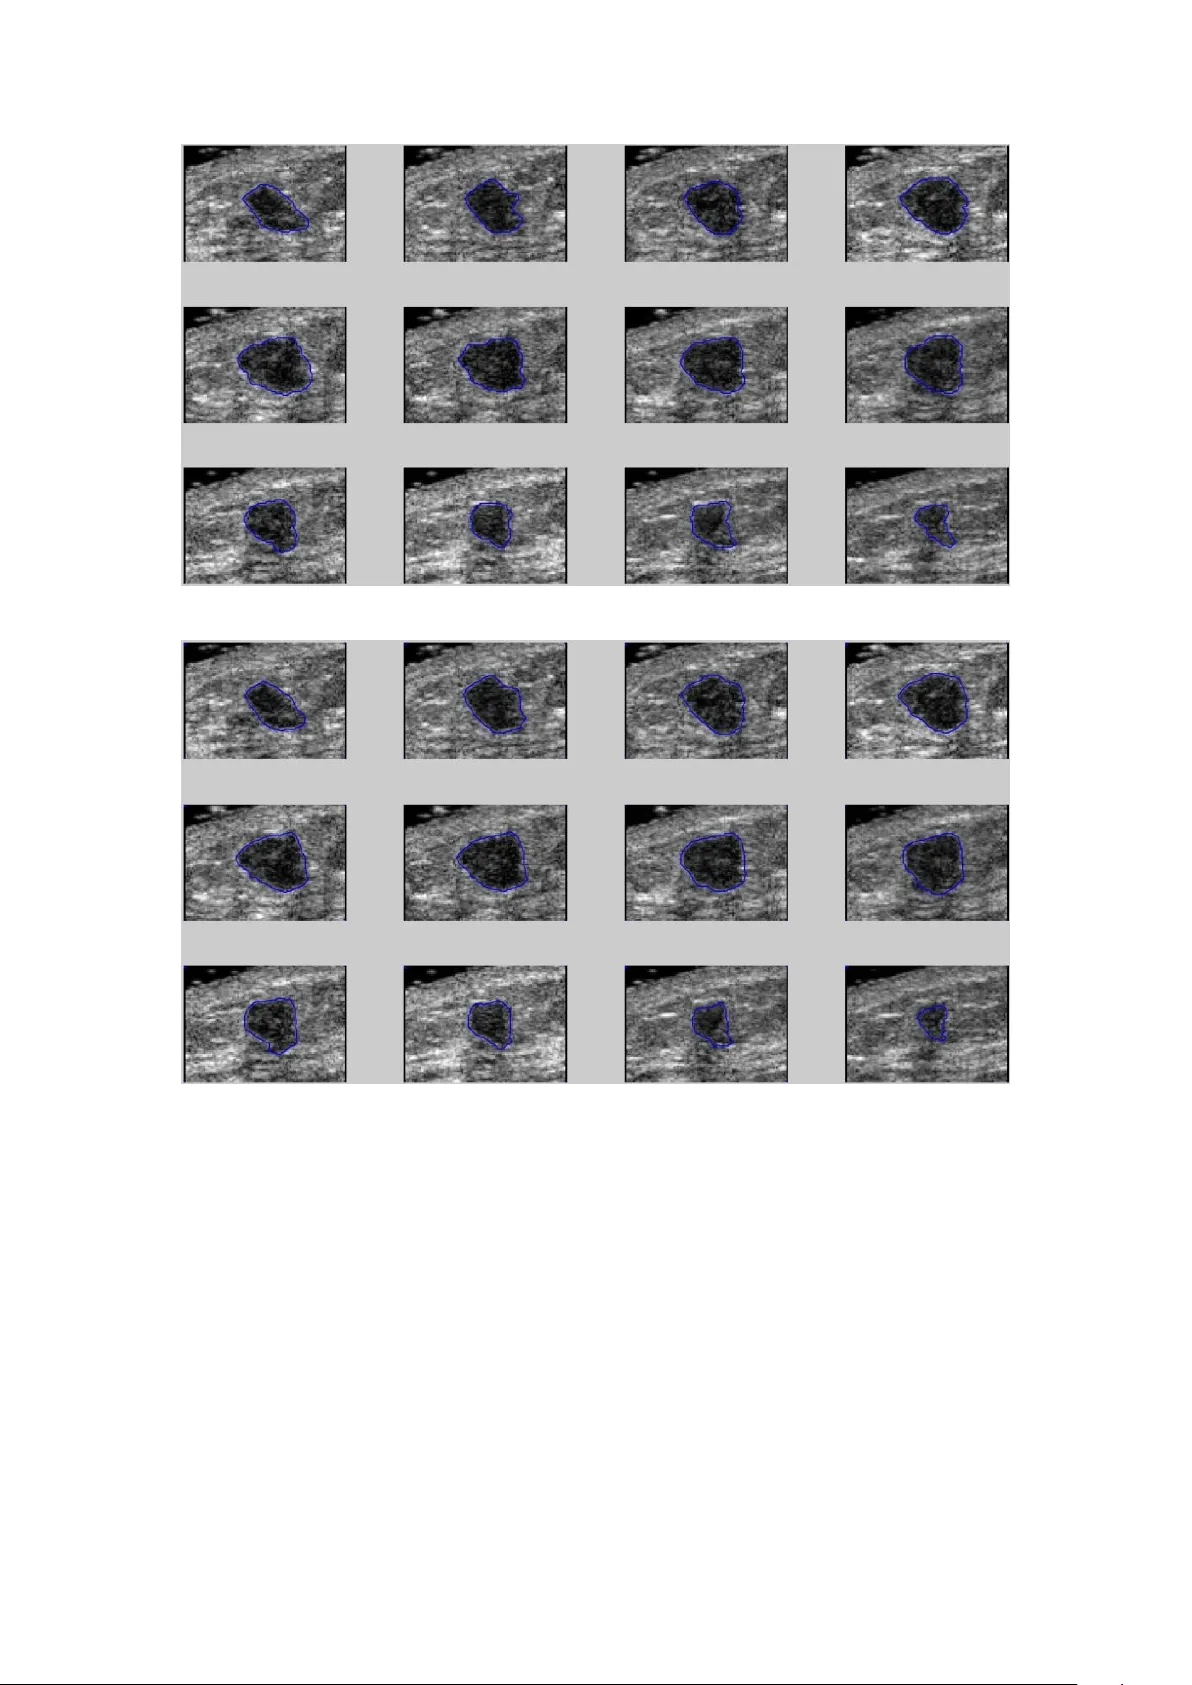

January 17, 2020 3D Contouring for Breas t Tumor in Sonog raphy Dar-Ren Chen, MD † , Yu -Chih Lin * Yu -Len and Hu ang, PhD * * Department of Computer Science, T unghai Universit y , T aichung, T aiwan † Comprehensive Breast Cancer Center , Laboratory of Cancer Research , Changhua Christian Hospital, Changhua, T aiwan Running title: Breast tumor segmentation The total number of words of the manuscript, including entire text from title page to figure legends: 4986 The number of words of the abstract: 177 The number of tables: 1 The number of figures: 8 Addre ss correspondence and r eprint r equests to : Professor , Y u-Len Huang Department of Computer Science T un ghai University No.1727, Sec.4, Taiwan Boulevard , Xitun District, T aichung 407, T aiwan T el: (886)-4-23590121 ex t. 33800 Fax: (886)-4-23591567 E-mail: ylhuang@thu.edu.tw Abstract Malignant and benign brea st tumors present differently in their shape and size on sonography . Morphological information provide d by tumor contour s are important in clinical diagnosis. However , ultrasound images contain noises and tissue texture; clinical diagnosis thus highly depends on the expe rience o f ph y sicians. The manual way to sketch three-dimensional (3D) contours of breast tumor is a time-consuming and complicate task. If auto matic contouring could provide a precise breast tumor contour that mi ght assist phy sicians in making an accurate diagnosis. This stud y presents an efficient method for automatically contourin g breast tumors in 3D sonogra ph y . Th e proposed method utiliz es an efficient segmentation procedure, i.e. lev el-set method (LSM), to a utomatic det ect contours of breast tumors. This study ev aluates 20 ca ses comprising ten beni gn and ten malignant tumors. The results of compute r simulation reveal that the proposed 3D segmentation method provides robust contouring for breast tumor on ult rasound images. This approach consistentl y obtains contours similar to those obtained by manual contouring o f the breast tumor and can save mu ch of the time required to sketch precise contours. Key Words: breast cancer , 3D sonogra phy , ima ge segmentation, level-set method, region growing Introduction Breast c ancer is a tumor emerged from growing mammar y epithe lial cells or lobular , they lost control because of the growth of c ancer cells and then will invade and damage nearby tissues and orga ns or metastasis to other organs through the blood or lymphatic s y stem. However , breast is ric h in blood vessels, lymphatic vessels and lymph nodes, breast cancer cells tend to spread to other organs easily . Breast cancer is one of the most fre quently o ccurring ca ncers in women. A ccording to the American Cancer Society (ACS) statistics, the prevalence of breast cancer rises up every y ear [1] . As medica l technology progress c ontinuousl y and personal health c oncern s increase constantly , making the breast cancer death rate decreased year by year . Thus early detection and early treatment for breast ca ncer would reduce breast cancer mortality . Medical ultra sound is certainly convenient and safe tool for dia gnosing breast tumors, particularly palpable tumors. Modern ultrasound equipment performs rea l-time high-resolution imaging without the use of ionizing radiation and it is relativel y inexpensive and portable. Ultrasound equipment becomes the essential dia gnostic tools for hospitals. Breast ultrasound is someti mes used to evaluate abnormal findings from a screening or diagnostic mammogram or ph y sical exam. Ultrasonic images are markers for the early detection of some breast cancers. The use of ultra so und for the early detection of some breast c ancers c an suppo rt in dif ferentiating between benign and malignant lesions by analy zing the homogeneit y of an internal echo. Computer- aided diagnosi s (CADx ) sy stem c ould assist physicians by extracting useful characteristics of the tumor in ultrasound image as a b asis for diagnosis [ 2, 3]. Three-dimensional (3D) ultrasound images of the breast cancer s creening h ave acquired attention. 3D ultrasonography provides similar imaging quality to conventional two - dimensional (2D) ult rasound and also has the mul ti-sectional c apability to revea l anatomical features what are not originally poss ible on a 2D s y stem. The volume dif ferences between malignant and benign breast tumors is considered a useful characteristic for identifying mali gnant breast tumors [4]. Thus a correct diagnosis might require accurate estimation of the total volume of the tumor and tumor contour . In conventional 2D ultra sound, the expert must mentally construct a 3D impression of tumor based on many 2D ultrasound images. The accuracy of CADx is re lated to the location and extent of tumor , the segmentation of the tumor ha s a direc t impact on the accuracy of diagnosis. Contour of breast tumor can be sketched in manual, semi-automatic, or fully automatic manner [5 - 8]. The manual segmentation method is not suitable for 3D ultrasound im ages. A 3D sonogram in one scan can take over hundreds of 2D image slices, which required plent y of time to sketch tum or c ontour manually . Thus automatic contouring which provided the similar contour with manual sketch of the breast tumor might assist physicians in making correct diag nose s [9 ]. However , ult rasound images comprise a lot of spots, noise, shadow and ti ssue tex ture; in addition, compared with the benign tumors, the edge of malignant tumors seemed more irregular , crushing and splitting, leading to the automatic segmentation method becomes a complicated work [ 10]. Most of segmentation methods on 3D ultrasound images utilized semi-a utomatic wa y to make up for technical shortcomi ngs. The operations of complexity and effic ien cy , the stable results of the execution are also worth consideration factors [1 1]. In computer vision, image se gmentation is the process of partiti oning a digit al image into multiple sections. The purpose of image segmentation is to simplify or change the representation of the image, making the im age easier to understand and analyze. There were many notable approaches for ultrasound imag e segmentation, such as clustering-ba sed image segmentation and region-based segmentation methods. Clustering-based imag e segmentation methods can be viewed as methods of minimizing the intensit y distance between each pixel and cluster center . K-means clustering [ 12, 13] , which is a clustering-based segmentation method, segmented image into K clusters through repea ted iteration until no chan ge s and then the method can create the ef fect of clust ering se gmentation. However , the K-means clustering data is also sensitive to noise and isolated points. This me thod must set the number of clusters, and excessive dependence on the initial value. Region-based segmentation according to the similarity of pixels, gathered the pixels into one area by exploiting the gra yscale bri ghtness, color and material. Equivalent to the whole i mage is divided into a block. W atershed transformations [14, 15], which is a popular region-based segmentation method, exercises the concept of topography and t reats digital im ag e as a topo graphic plane. The pix el with highest v alue is the highest point on the terrain, the lar ger the change of the values indic ates a stee per terrain. However , watershed transformation is ver y sensitive to noise, which would cause over- segmentation to obtain inaccurate contours [16 ]. Active contour model (ACM) algorithm [ 17], also known as snake algorithm, mainly used in two -dimensional image analysis and machine vision image boundary detection, the purpose is to find the object boundary . Although active contour can be more accurately s earch the boundar y of the object, the drawback is the need to provide the ini tial boundary and works on single targ et onl y . Moreover , the ACM-deformation procedure is ve r y time -consuming. The aim of thi s study w as to develop a n efficient segmentation scheme for 3D breast ult rasound imaging . This stud y describes a contour initi alizing procedure b y using 3D re gion growing techniques, as part of the proposed contouring method, to generate formal initial contours for breast tumors. Level set method (L SM), a n ef ficiently developed deformable model that surpa ssed ACM in segmentation performance, is utilized to conserve the time required to sk etch a precise contour. The proposed method performed 3D version of the LSM to ex tract contours of a breast tumor from 3D ultrasound imaging with very high stability . This stud y then compared the automatic breast contouring results with those sketched by an expert radiologist. Materials and Meth ods Data Acquisition This study collec ted ten benign and ten malig nant breast tumor patients aged from 20 to 78 years old (mea n age 42 years). The e ntire database was approved by the institutional review board and ethics committee at Changhua Christian Hospital, Taiwan. Informed consent was obtained from all patients. If the patient h ad multi ple breast lesions, the biggest lesion was included in the study. Approximatel y 120 to 280 ultrasound im ag es of each ca se and the average ima ge size is 366×216 pixels. Sonographic examinations were don e b y using 3 D power Doppler ult rasound with the high definition flow ( HDF ) function (V oluson 730, GE Medical Systems, Zipf, Austria). A linear-array broadband probe with a frequency of 6–12 MHz, a scan width of 37.5 mm, and a sweep angle of 5◦ to 29◦ to obtain 3D volume scanning was used. Physician kept a fixed sweep angle of 20◦ and pow er Doppler settings of mid frequency , 0.9 kHz pulse repetition frequency , -0.6 gain, and ‘low 1’ wall motion filter in all cases. All obtained images were stored on the hard disk and transferred to a pe rsonal computer using a D ICOM (Digital Imaging and Communications in Medicine) connection for image analysis. The Pr oposed Segmentation Method The qualit y of initial contour not only influences to the final segmentation result, but a lso relates to computation time of segmentation. The proposed method utilized the 6-neighbors 3D region growing method to generate initial contour . M orphological closing operator [18] was used to refine the extra cted contour which generated by 3D region growing procedure. The closing operator could eliminate small holes, cracks, and elongated pit; and the n fill ed the gap on the con tour to smooth the boundary . Finally , this study performed LSM a lgorithm by using the e xtracted initial contour to obtain the desired segmentation results. Figure 1 shows the flowchart of the proposed method . Initial Contouring Region g rowing technique [19, 20] is a simple and ef fective method for e xtracting initial contours. The procedure starts with a set of seed points and then group ed neighboring vox els or sub-regions which provided similar properties. T o determine that the seed su rrounding pixels whether to have sim ilar characteristics with th e seed, li ke gray-scale values, joints a nd colors. If the su rrounding voxels had similar characteristics with the se ed, the surrounding vox el w as accepted into the same region. 3D r egion growing method [21] was used to separate the breast tumor region from background . T o extract initial contour of the tumor desi gnate in 3D ult rasound imaging, a physician experienced in breast ultrasound examination defined and manually selected seed points which approached tumor c enter . The 3D regional gro wing procedure in this study performe d six 6-neighboring model (6 -connectivity) [22] along the selected seed point, i.e. front, rear , left, right, upper and lower direction s, to find a similar part with similar characteristics (see Fi g. 2). The intensit y property was used to include a vox el in either region if the absolute difference in intensity between a vox el and the seed point is less than a predefined property threshold T . Adjacent voxels that satisfied the intensity propert y for the sub-region was assigned int o tumor region A. If difference between any of the adja cent voxels and the seed point was less than the threshold T , the proposed method put the adjacent voxel incorporated into the same region with the seed point and re-calculated mean intensity of A . Then the ne w incorporated voxel wa s used as a new starting point t o look for its six adjacent voxels. The entire procedure was repeated until no further changes o ccurred . Due to 6-nei ghboring model is faster than the traditional 26-neighboring model, the proposed procedure required a small amount of computation time to generate a reasonable ini tial c ontour of bre ast tumor in 3D ultrasound imaging. 3D R efining Segmentation The proposed method p erformed 3D LSM algorithm to obtain refined cont our of breast tumor . The LSM is a numerical technique for computing and analy zin g the curve propagation [23]. The basic idea of LSM is that the plane closed curve ex pressed as a 3D continuous function surfaces which having the same function va lue curve φ ( x , y ) is usually φ = 0 , known as t he zero level-set, and the φ ( x , y ) is also called level-set function. The LSM is a wa y to denote active contours [24] . The zero level-set contour of th e function is defined by C 󰇝󰇛 x, y 󰇜 φ 󰇛 x, y 󰇜 = 0 󰇞 . (3) Moreover , inside region and outside region of the curve is defined as 󰇱 φ 󰇛 x, y 󰇜 >0 outside region φ 󰇛 x, y 󰇜 =0 contour  φ 󰇛 x, y 󰇜 <0 inside region (4) In the LSM, φ = 0 represents the desired contour , φ < 0 is the internal region of the contour , and φ > 0 is the external region of the contour . Figure 3 shows that the value of level-set function was used to outline the desired contour . T ake a closed curve as a boundary , the entire plane is divided into two area s: the external and internal regions of the curve . In the plane defined distance function φ ( x , y , t ) = ±d , where d is the poi nt ( x , y ) to the shortest distance of the curve, function symbols depending on the point in the curve of the internal or external, generally defined curve interior points the distance is negative, t represents time. At any moment, the point on the curve is the zero point of dist ance function value, i.e. a function of distance to the zero level set. Level-set method not only can handle a sharp endpoint and concave angle, but also can be automated to change the topology . There are two main advantages to represent the a ctive contour b y l evel set met hod. First, it can easily represent complicated contour changes, for example when the c ontour splits into two or develops holes inside. Second, we can e asily know whether a point is inside or outside the contour by checking the φ value. Th is stud y uti lized Chen-V ese m ethod [25] which the level -set function φ is updated as   󰇛 󰇜  󰇥   󰇡     󰇢    󰇛     󰇜     󰇛     󰇜    󰇦 , (5) where u 0 is the original image, c1 and c2 are the average gray level intensit y in φ >0 region and φ <0 region, respectively . More over , μ and v is length penalty and a rea penalty , respectively . The fit parameters λ 1 a nd λ 2 is used to adjust the weights of terms . Dirac delta function δ is performed to make th e contour smooth and eliminate some small isolated reg ions. The se cond and the third terms a re the driving force term whic h drives contour to move towards the equilibrium point. In the propos ed c ontouring method, the original ultrasound im age is fi rst processed b y the 3D region growing. After the initial contouring, the 3D level set method is performed to segment the tumor . Contour Evaluation An experience d physician who was familiar with breast ultrasound inte rpretations manually determined 3D c ontours of the tumor by using two modes. The entire manual sketching (EMS) mode denoted physician manually sketched 2D contour on eac h slice of a tumor . The obtaine d contours from the EMS mode was perf ormed as ground truth. The partial manual sk etching mode denoted the virtual organ computer-aided analysis (VOCAL) [26-28] scheme within 4D V i ew software (G E Medical Systems, Zipf, Austria) was per formed to obtain an approximated 3D contour . The VOCAL scheme estimates 3D contours by a selectable de gree of rotation. This stud y ado pted a ver y common rotation degree 30 o , the six preliminary tumor contours in 0 ◦ , 30 ◦ , 60 ◦ , 90 ◦ , 120 ◦ and 150 ◦ slice images were manually sketc hed . Figure 4 represents the tumor contour manually sketched with 30 ◦ rotation. The VOCAL mode utilized the six extracted tumor regions to build a 3D interested reg ion volume. The obtained contours from two mode s were saved in files for comparison with the automatica ll y generated contours. Four practica l similarity me asures [29], the similarity index (SI), overlap value (OV), overla p fraction (OF) and extra fraction (EF) between the manually determined contours and the automaticall y detected contours were calculated for quan titative analysis of the co ntouring results. REF represents the results depicted b y th e EMS mode , and SEG in dicates the results from the VOCA L mode or the proposed segmentation method. Overlap area denot es the area covered by SEG and REF , extra area denotes the false positive area and missing area denotes false negatives area. Figure 5 il lustrates the relationship between the S EG and REF . When S I, OV and OF are close to 1, and EF c omputation is close to 0, it means that the contours generated by automatic segmentation is similar to the manual contours b y physician. The overlap denotes the area of the intersection of the reference and the automated segmentation. The S I expresses the sim ilar de gree between SEG and REF areas. The OV is identical to the Jaccard index, a lso known as Inter section over Union (IoU). The SI, OF , OV and EF are defined as SI  =  2   REF∩ SEG  REF+SEG  , (5) OF  =  REF∩SEG REF    , (6) OV  =  REF∩SEG REF ∪ SEG    and (7) EF  =  REF         ∩S EG REF    . (8) Results This study utilized the simil arity measure s to evaluate the tum or contours generated b y the proposed segmentation method and the VOCAL method with 30 o rotations. The simulations tot ally evaluated 20 cases with manual sketched contours form EMS mode (including 10 benign breast tumors and 10 malignant ones) to test the accuracy of the proposed contouring method. In thi s stud y , the region growing threshold T was ex perimentally set to 5.0, and the size of structur e element for closing op erator was 20 × 20. 3D G aussian blur filtering with sigma value 1.5 was performed to diminish noises in imag ing before level-s et segmentation. And then we emplo y ed the level set method to achieve a precise segmentation for the tumor . W ith the curvature parameters length penal ty µ = 0.2, area penalty ν = 0, fit weights λ 1 = λ 2 = 1 , the proposed level scheme obtained a stable and the highest accuracy . T able 1 shows contouring performance of the proposed method and V OCAL method. The average of the mea sures (SI , OV , OF , EF) that determined by the proposed method and the VOCAL method were (0.85, 0.9 2, 0.75, 0.13) and (0.81, 0.84, 0.69, 0.34), respectively . The simulations were made on a sin gle CPU Intel® Xeon® Processor E3-1225 v5, 3.30 GHz personal computer with Microsoft W indows 10 professional ope rating system and th e pro gram development enviro nment was MA TLAB (R2016.a) software (The MathW orks, Inc., Natick, MA). A verage execution time for e ach case was 25.3 seconds. As thi s scheme is an of fline diagnostic application, these segmentation times are c linicall y acceptable. Figure 6(a) is the contour of a benign tumor which drawn manuall y b y a d octor . Figure 6(b) is the result obtained by the proposed method. Figure 6(c) is contour result obtained by usin g VOCA L method. Besides, Fig. 7(a ) is the contour of a malignant tumor which drawn manuall y b y a docto r . Figures 7(b) and 7 (c) are the obtained result by the proposed method and VOCAL method, respectively . Figure 8 shows the detail results of the assessment of the proposed method and the VOCAL method. The proposed method clearly yield ed contours that a re more similar to those manuall y sketched than that of obt ained by VOCA L method. From the seg mentation results, onl y a small number of cases might generate an undesired segmentation. Conclusion Today, in many dia gnostic modalities of breast cancer, advanta ges of ult rasound are ima ges-cost, easy to operate, non-radioactive, immediate an giography and non- invasive. Physicians generally utilized ultrasound i mages in tum or diagnosis and tes ting, moreover clinicians take it to test tumor biopsies to determine tumor benign and malignant. If a computer-aided s ystem was useful to correct depi ction of tumor contour, it would be help on improving physician di agnosis of benign and malignant tumors of the correct rate. This study proposed a fast and high accurac y automatic 3D breast tumor image segmentation method. The proposed method performed the region growing produce to obtain the initi al outline and get the final contouring results b y usin g level- set method. This work kept away from the problem of level -set algorithm which needs a large amount of computation in 3D space, as well as resolved its problem of ex cessive dependence of initial contour in image segmentation. According to the experimental 10 benign c ases and 10 malignant cases showed that the methods used in t his study can effectively cutting ultrasound imaging of tumor contours, its average value of SI can reach more than 85%; compared to the VOCAL method of the EF a verage 34%, the propos ed m ethod can significantly reduce the value of the EF to 12%. For tumor contour cutting error has significantl y impro ved. In our study, each case computi ng time required is approx imately 25 seconds. C ompared to other method of cutting, usuall y n eed several minutes. Our propo sed method has significant adva ntages, and for medic al dia gnostic a pplications have more practical assistance. The proposed method was fully automated 3D br east tumor contour cutting. User only need ed to select a region growing s eed point, you will ge t breast cancer 3D contour cutting. Compared VOC AL method requires manual depicting six ultrasound images of the diffe rence of tum or c ontours, and physicians ne ed to manually describe each one tumor contour method of rapid a nd convenient, which would help doctors in the diagnosis of convenience. Due to the reduced time required for the progra m operation, the proposed method does not carry out pre-processing for the image, which cause s the accuracy rate resulting of breast tumors contour will be decre ased. Therefore, the future will face in combination with other effective filte r to reduce noise, without increasin g too much computation time of the situation and effectively enhance tumor contour cutting accuracy. Ack now ledgement The authors would like to thank the Ministry of Science and T echnolo gy , T aiwan for financially supporting this research under Contract No. MOST 106- 2221-E-029-029. Refer ences 1. ACS, B reast Cancer Facts and Fig ures 2017-2018', (Atlanta: American Cancer Society , 2017) 2. Shan, J., Alam, S.K., Garra, B., Zhang, Y ., and Ahmed, T ., 'Computer-Aided Diagnosis for Breast Ultrasound Using Computeriz ed Bi -Rads Features and Machine Learning Methods', Ultrasound Med Biol , 2016, 42, (4), pp. 980-988. 3. Choi, J.H., Kang , B.J., B aek, J.E., Lee, H.S., and Kim, S.H., 'Application of Computer- Aided Diagnosis in Breast Ultrasound I nterpretation: Improvements in Diagnostic Performance According to Reader Experience', Ultrasonography , 2018, 37, (3), pp. 217-225. 4. Hsiao, Y .H., Huang, Y .L., Kuo, S.J ., Liang, W .M., Chen, S.T ., and Chen, D.R., 'Characterization of Benign and Malignant Solid B reast Masses in Harmonic 3d Power Doppler Imaging', Eur J Radiol , 2009, 71, (1), pp. 89-95. 5. Horsch, K., Giger , M.L., V enta, L.A., and V yborny , C. J., ' Automatic Segmentation of Breast Lesions on Ultrasound', Med Phys , 2001, 28, (8), pp. 1652-1659. 6. Chang, R.F ., W u, W .J ., T seng, C.C., Chen, D.R., and Moon, W .K., '3 -D Snake for Us in Marg in Evaluation for Malignant Breast T umor Excision Using Mammotome', IEEE T rans Inf T echnol Biomed , 2003, 7, (3), pp. 197-201. 7. Madabhushi, A. and Metaxas, D.N., ' Combining Low-, High-Level a nd Empirical Domain Knowledge for Automated Segmentation of Ultrasonic Breast Lesions', IEEE T rans Med Imaging , 2003, 22, (2), pp. 155-169. 8. Chen, T . and Metax as, D., 'A H ybrid Framework for 3d Medical Image Segmentation', Med Image Anal , 2005, 9, (6), pp. 547-565. 9. Xian, M., Zhang, Y ., C heng, H.D., Xu, F ., Z hang, B., and Ding, J., 'Automatic Breast Ultrasound Image Segmentation: A Surve y', Pattern Recognition , 2018, 79, pp. 340-355. 10. Huang, Y .L., Chen, D.R., and Chang, S.C., ' Three-Dimensional Re gion-Based Segmentation for Breast T umors on Sonography', J Ultrasound M ed , 2013, 32, (5) , pp. 835-846. 1 1. Xu, Y ., W ang, Y ., Y uan, J., Cheng, Q., W ang, X., and Carson, P .L., 'Medical B reast Ultrasound Image Segmentation by Machine L earning', Ultrasonics , 2018, 91, pp. 1-9. 12. Pang, Y ., Li, L., Hu, W ., Peng, Y ., L iu, L., and Shao, Y ., 'Computerized Segmentation and Cha racterization of Breast Lesions in Dynamic Contras t -Enhanced Mr Imag es Using Fuzzy C -Means Clustering and Snake Algorithm', Comput Math Methods Med , 2012, 2012, p. 634907. 13. Boukerroui, D., Basset, O., Guerin, N., and Baskurt, A., 'Multiresolution T exture Based Adaptive Cluste ring Algorithm for Br east Lesion Se gmentation', Eur J Ultrasound , 1998, 8, (2), pp. 135-144. 14. Rodriguez, R., Alarcon, T .E., and Pacheco, O., 'A New Strategy to Obtain Robust Markers for Blood V ess els Segmentation b y Usin g the W atersheds Metho d', Comput Biol Med , 2005, 35, (8), pp. 665-686. 15. Navlakha, S., Ahammad, P ., a nd M y ers, E.W ., 'Unsupervised Segmentation of Noisy Electron Microsc opy Images Using S alient W atersheds and R egion Merging', BMC Bioinformatics , 2013, 14, p. 294. 16. Huang, Y .L. and Chen, D.R., 'W atershed Segmentation for Breast T umor in 2 - D Sonography', Ultrasound Med Biol , 2004, 30, (5), pp. 625-632. 17. Maksimovic, R., Stankovic, S., and Milovanovic, D., 'Computed T omograph y Image Analyzer: 3d R econstruction and Segmentation Appl y ing Acti ve Contour Models -- 'Snakes'', Int J Med Inform , 2000, 58-59, pp. 29-37. 18. Aktouf, Z., Bertrand, G., and Perroton, L., 'A Th ree-Dimensional Holes Closing Algorithm', Pattern Recognition Letters , 2002, 23, (5), pp. 523-531. 19. Sajadi, A.S. and Sabzpoushan, S.H., 'A New Seeded Region Growing T echnique for Retinal Blood V essels Ex traction' , J Med Signals Sens , 2014, 4, (3), pp. 223 -230. 20. Park, S., Lee, J., Lee, H., Shin, J., Seo, J ., Lee, K.H., Shin, Y .G., and Ki m, B., 'Parallelized Seeded Reg ion Growing Using Cuda', Comput Math Methods Med , 2014, 2014, p. 856453. 21. Muhlenbruch, G., Das, M ., Hohl, C ., W ildberg er , J.E., Rinck, D., Flohr , T .G., Koos, R., Knackstedt, C., Gunther , R.W ., and Mahnken, A.H., 'Global Left V entricular Function in Cardiac Ct. Evaluation of an Automate d 3d Region-Growing Segmentation Algorithm', Eur Radiol , 2006, 16, (5), pp. 1 1 17-1123. 22. Cohen-Or , D. and Kaufman, A., '3d Line V oxelization and Connectivit y Control', IEEE Computer Graphics and Applic ations , 1997, 17, (6), pp. 80-87. 23. Osher , S. and Sethian, J .A., 'Fronts Propaga ting with Curvature-De pendent Spe ed: Algorithms Based on Hamilton-J acobi Formulations', Journal of Computational Physics , 1988, 79, (1), pp. 12-49. 24. Huang, Y .L ., J iang, Y .R., Chen, D.R., and Moon, W .K., 'Leve l Set Contouring for Breast T umor in Sonography', J Digit Imaging , 2007, 20, (3), pp. 238-247. 25. Chan, T .F . and V ese, L .A., 'Active Contours without Edges', IEEE T ransactions on Image Pr o cessing , 2001, 10, (2), pp. 266-277. 26. Raine-Fenning, N.J., Clewes, J.S ., Ke ndall, N.R., Bunkheila, A.K., Campbell, B.K., and Johnson, I.R., 'The Interobserver Reliabilit y and V alidity of V olume Calculation from Three-Dimensional Ultrasound Datasets in the in V itro Setting', Ultrasound Obstet Gynecol , 2003, 21, (3), pp. 283-291. 27. Raine-Fenning, N., Cam pbell, B., Collier , J ., Brincat, M., and J ohnson, I., 'The Reproducibility of Endometrial V olume Acquisition and Measurement with the V ocal - Imaging Program', Ultrasound Obstet Gynecol , 2002, 19, (1), pp. 69-75. 28. Bordes, A., Bory , A. M., Benchaib, M., Rudigoz, R.C., and Salle, B ., 'Reproducibility of T ransv aginal Three-Dimensional Endometrial V olume Measurements with V irtual Organ Computer-Aided Anal y sis (V ocal) Duri ng Ovarian Stimulation', Ultrasound Obstet Gynecol , 2002, 19, (1), pp. 76-80. 29. Anbeek, P ., V inck en, K.L., van Osch, M.J ., Bisschops, R.H., and van der Grond, J., 'Probabilistic Segmentation of W hite Matter Lesions in Mr Imaging', N eur oimage , 2004, 21, (3), pp. 1037-1044. List of T ables Table 1. The contouring e valuations of the proposed met hod and VOCA L metho d using the similarity measurements (average). List of Figures Figure 1. Flowchart of the proposed method Figure 2. Neighbors (the blue voxels) within the 6-connectivit y Figure 3. Illustrations of the level-set method Figure 4. The tumor contour which manually sketched with 30◦ by export Figure 5. Schematic diagram evaluation of contour Figure 6. Results of contour segmentation with a benign case: (a) is the benign tumor contour that drawn manuall y by a doctor; (b) is the result of obtained benign tumor contour segmentation b y our p roposed LSM method; (c) is a benign tumor contour results obtained by using the VOCAL method Figure 7. Results of contour segmentation with a malignan t case: (a) is the malignant tumor contour that drawn manually b y a doctor; (b) is the result of obtained malignant tumor contour segmentation by our proposed LSM method ; (c) is a malignant tumor contour results obtained by using the VOCAL method Figure 8. Similarity eva luation results of the assessment of the propose d LSM method and VOCAL method: (a) S imil arity index (SI), (b) O verlap value (OV), (c) O verlap fraction (OF) and (d) E xtra fraction (EF) T able 1. The contouring evaluations of the proposed method and VOCAL method using the similarity measurements (average) . Pathology proven result Benign case (10 cases) Malignant case (10 cases) Whole database (20 cases) SI The proposed method 84.67% 85.66% 85.17% VOCAL mode 80.81% 81.91% 81.36% OF The proposed method 87.66% 96.08% 91.87% VOCAL mode 82.40% 85.79% 84.09% OV The proposed method 73.75% 75.34% 74.54% VOCAL mode 68.36% 69.47% 68.91% EF The proposed method 1 1.65% 13.88% 12.76% VOCAL mode 28.41% 38.88% 33.64% SI: similarity index; OF: overl ap fraction; OV : overlap val ue; EF: extra fraction Figure 1. Flowchart of the proposed method Segment ation Results 3D leve l - set meth od Initial con tour 3D region gr owing Select the seed points 3D ultr asonic imaging Middle-1 slice Middle+1 slice Middle slice #1 slice #n slice . . . . Figure 2. Neighbors (the blue voxels) within the 6-connectivity Figure 3. Illustrations of the level-set method Figure 4. The tumor contour which manuall y sketched with 30◦ b y e xport miss overlap extra REF SEG Figure 5. Schematic diagram evaluation of conto ur (a) (b) Figure 6 Results of contour segmentation with a benign case: (a) is the benign tumor contour that drawn manuall y by a doctor; (b) is the result of obtain ed benign tumor contour segmentation by our proposed L SM met hod; (c) is a benign tum or contour results obtained by using the VOCAL method ( continued) (c) Figure 6. Results of contour se gmenta tion with a benign case: (a) is the benign tumor contour that drawn manuall y by a doctor; (b) is the result of obtain ed benign tumor contour segmentation by our proposed L SM met hod; (c) is a benign tum or contour results obtained by using the VOCAL method (a) (b) Figure 7. Results of contour segmentation with a malignant case: (a) is the malignant tumor contour that drawn manually by a doctor; (b) is the result of obtained malignant tumor contour segmentation b y our proposed LSM method ; (c) is a malignant tum or contour results obtained by using the VOCAL method ( continued) (c) Figure 7. Results of contour segmentation with a malignant case: (a) is the malignant tumor contour that drawn manually by a doctor; (b) is the result of obtained malignant tumor contour segmentation b y our proposed LSM method ; (c) is a malignant tum or contour results obtained by using the VOCAL me thod (a) (b) Figure 8. Similarity evaluation results of the assessment of the proposed LS M method and VOCAL method: (a) S imilarity index (S I ), ( b) Overlap value (OV), (c) Overlap fraction (OF) and (d) Extra fraction (EF) ( continued) 0% 10% 20% 30% 40% 50% 60% 70% 80% 90% 100% SI: Sim ilarity Index LSM VOCAL 0% 10% 20% 30% 40% 50% 60% 70% 80% 90% 100% OF: Overlap Fraction LSM VOCAL (c) (d) Figure 8. Similarity evaluation results of the assessment of the proposed LS M method and VOCAL method: (a) S imilarity index (S I ), (b) Overlap value (OV), (c) Overlap fraction (OF) and (d) Extra fraction (EF) 0% 10% 20% 30% 40% 50% 60% 70% 80% 90% 100% OV : Overlap V alue LSM VOCAL 0% 10% 20% 30% 40% 50% 60% 70% 80% 90% 100% EF: Extra Fraction LSM VOCAL